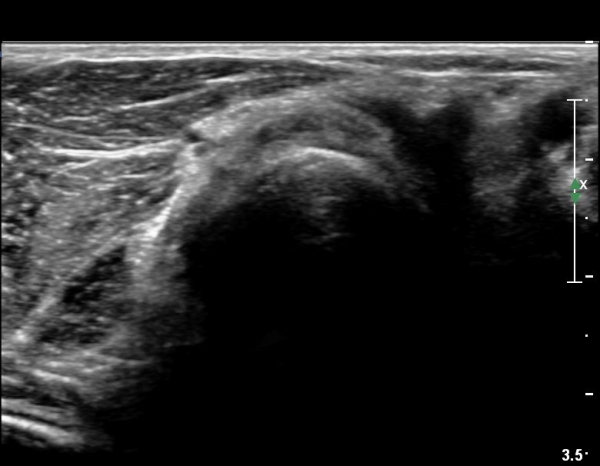

Á¶±Ý´õ ŽÃËÀÚ¸¦ ¸»´ÜÀ¸·Î À̵¿ÇÏ´Ï ³¶Á¾Àº ÀÛ¾ÆÁö°í ȸ¿Ü±Ù »çÀÌ¿¡ À§Ä¡ÇÏ´Â Èİñ°£ ½Å°æÀÇ

ºÎÁ¾ÀÌ °üÂûµÈ´Ù(»çÁø 6)

Èİñ°£ ½Å°æ Á¾´Ü¸é°Ë»ç¿¡¼­ ³¶Á¾¿¡ ÀÇÇÑ Èİñ°£ ½Å°æ ¾Ð¹Ú°ú  Èİñ°£ ½Å°æÀÇ ºÎÁ¾ÀÌ °üÂûµÈ´Ù(»çÁø 7).